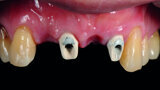

Fig. 1: Pre-op frontal view of the anterior teeth.

Fig. 2: Pre-op occlusal view of the anterior teeth.